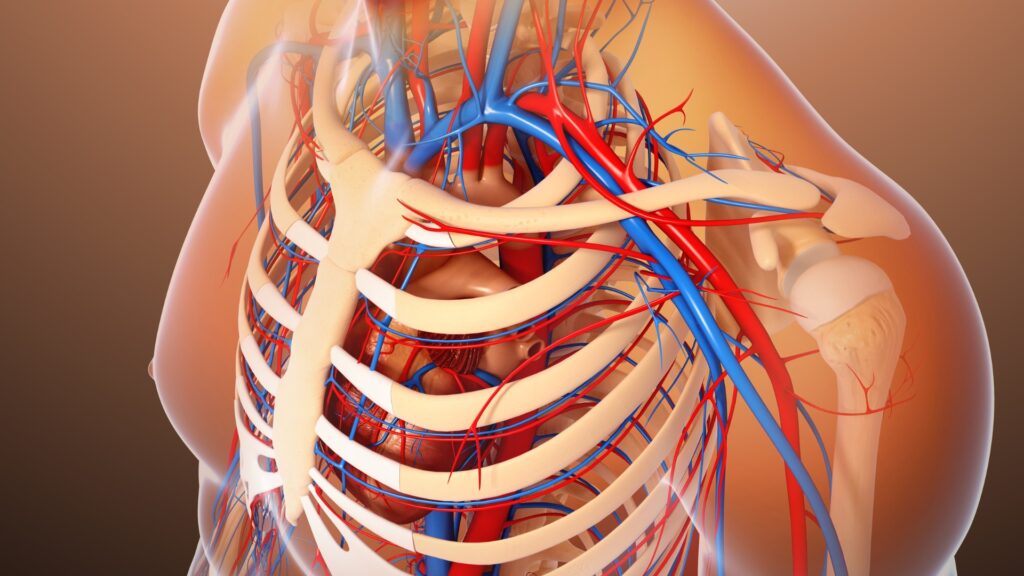

Realizado por um especialista em ultrassonografia vascular, o Doppler colorido utiliza ondas sonoras para criar imagens detalhadas das veias cavas. Durante o procedimento, o paciente permanece em uma posição confortável enquanto um gel condutor é aplicado na área a ser examinada. Um transdutor é movido ao longo da pele para capturar imagens, e a adição de uma codificação de cores permite observar o fluxo sanguíneo e identificar possíveis anomalias, como tromboses ou estenoses.

- Detecção de Tromboses: Identificação eficaz de coágulos sanguíneos nas veias cavas, prevenindo complicações graves, como a embolia pulmonar.

- Identificação de Estenoses: Detecta estreitamentos nas veias, o que pode comprometer o fluxo sanguíneo e exigir intervenção precoce.

- Análise do Fluxo Sanguíneo: Fornece informações detalhadas sobre a velocidade e a direção do fluxo, fundamentais para um diagnóstico preciso.